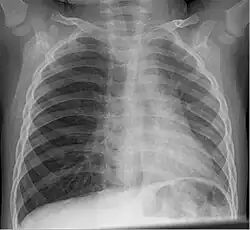

Aufmerksam sollten Anwesende werden, wenn es bei einer Person zu einer plötzlichen Hustenattacke kommt, die mit Atemnot einhergehen kann, aber nicht muss. Eine radiologische Untersuchung mittels Röntgen-Thoraxübersichtsaufnahme, Röntgen-Thoraxaufnahme in Exspiration oder einer Durchleuchtung sind erste diagnostische Maßnahmen. Eine Szintigraphie ist eine weitere Möglichkeit. Die Krypton-81-m-Ventilationsszintigraphie hat eine besonders hohe Detektionsrate. Schließlich sollte eine Bronchoskopie neben der diagnostischen Klärung auch den therapeutischen Erfolg bringen.

- Verbleibt der Fremdkörper oder das Aspirat in der Lunge, so kann dies eine Lungenentzündung (Pneumonie) nach sich ziehen. Ursache dieser Entzündung können chemische Reize (durch Magensäure bzw. Säureaspiration[8]) oder eine Infektion sein. Wird das Aspirat nicht entfernt, können wiederkehrende Lungenentzündungen (Aspirationspneumonien), Atelektasen, Granulationen und Stenosierungen bis hin zum Lungenversagen (ARDS) die Folge sein.